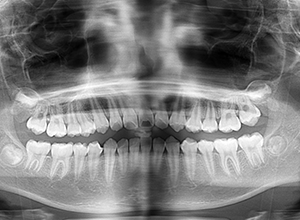

X-Ray

X-Ray所見

セファロ所見 SNAは84.3°、SNBは77.2°、ANBは7.1°とskeletal ClassⅡ、垂直的にはロウアングルの骨格形態をしていた。 上顎前歯は唇側傾斜を呈していた。

パノラマ所見 後継永久歯の歯数や萌出方向の異常は認められなかった。